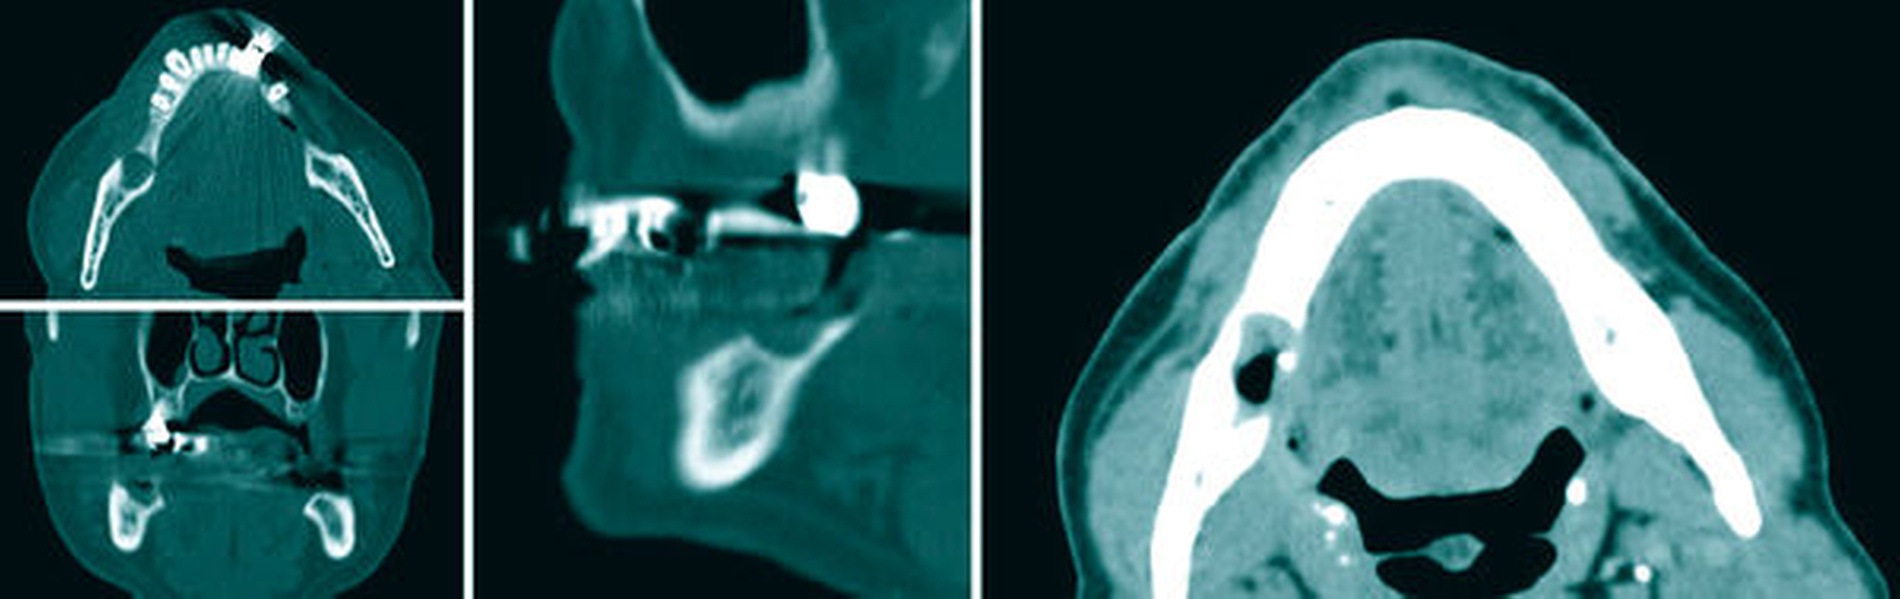

Im Rahmen des Tumorstagings erfolgten ein Kontrastmittel-unterstütztes Hals- und Thorax-CT, eine Abdomensonografie, eine HNO-ärztliche Spiegeluntersuchung sowie eine Ösophagogastroduodenoskopie. Bis auf den intraoralen Befund zeigten sich alle weiteren Diagnostiken als unauffällig (Abbildung 2). Die präoperative Vorstellung des Patienten in der Tumorkonferenz ergab die Empfehlung zur operativen Intervention. Das erstellte Angio-CT der unteren Extremitäten zeigte bei geringgradigen altersgemäßen Stenosierungen eine beidseitige crurale Dreigefäßversorgung. Aus den teleradiologisch übermittelten DICOM-Daten des Hals- und Angio-CT wurden präoperativ sowohl die Cutting Guides für die mandibulären Resektionsgrenzen als auch für das zweisegmentierte Fibulatransplantat angefertigt.